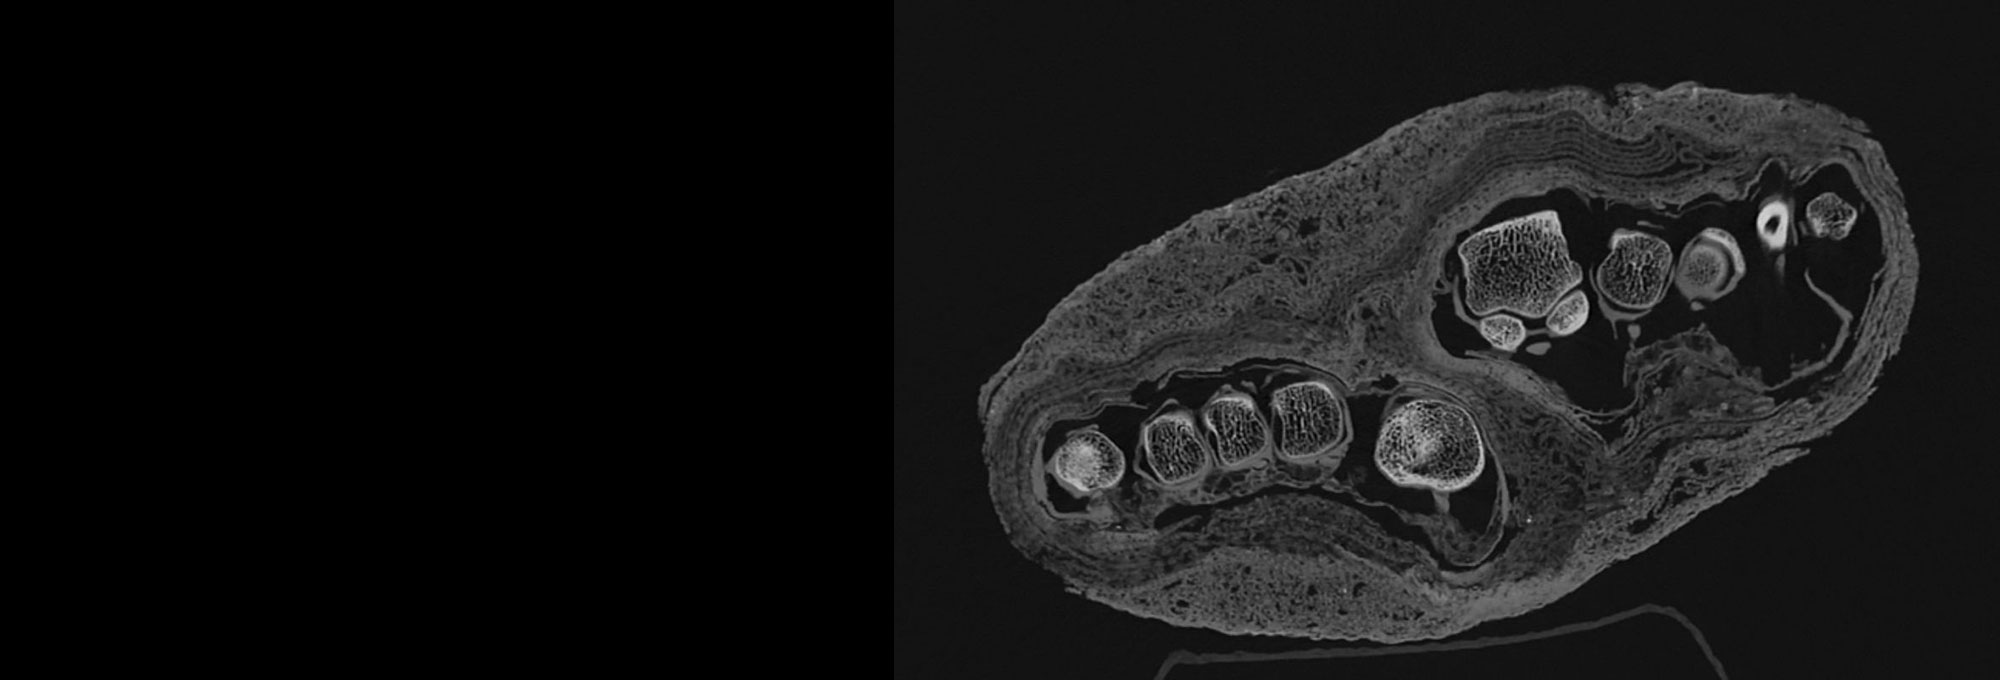

BUDAPEST, HUNGARY—Ancient Egyptian mummified remains in the collection of the MNMKK Semmelweis Museum of Medical History were examined with a CT scanner equipped with a photon-counting detector, according to a statement released by Semmelweis University. The remains in the study include two heads, two left lower limbs, a mummy bundle containing a foot, and a hand. The oldest artifacts in the collection are some 2,300 years old. The resulting images revealed the internal structure of the body parts, said team physician Ibolyka Dudás, providing a highly detailed view of abnormalities and preservation techniques used in antiquity. The new images of the lower limb suggest that the individual had osteoporosis. A second lower left limb was found to have belonged to a younger person. Images of the mummy bundle revealed layers of different types of bandages. The new information gathered could allow researchers to determine if the hand belonged to a child or an adult. “Based on the results so far, it is evident that modern imaging technology opens up new perspectives in mummy research,” said Krisztina Scheffer of the MNMKK Semmelweis Museum of Medical History. “It can reveal information hidden in finds that are thousands of years old without damaging them,” she concluded. To read about CT scanning of the sarcophagus containing the mummified body of Amenhotep I, go to "Inside a Pharaoh's Coffin," one of ARCHAEOLOGY's Top 10 Discoveries of 2022.